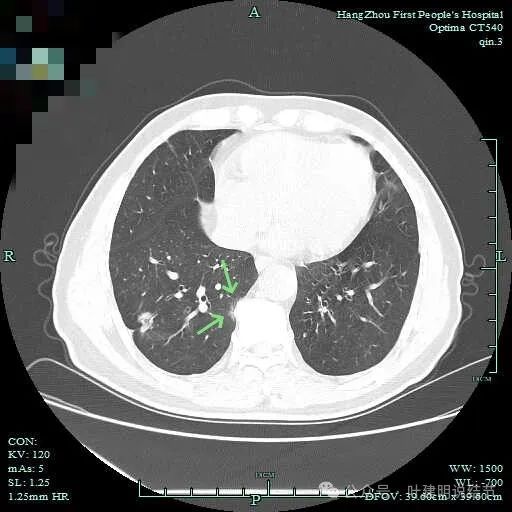

次病灶连续层面观察:

与脊柱间似乎有间隙在,另见微小血管进入这条索状的偏高密度影处。

有细小血管进入,但说不上异常增粗。病灶仍是小片状,条状。

上图见细毛刺明显。

病灶实性伴细毛刺,与脊柱间有间隙在。

上图呈结节状,表面不平,有少许磨玻璃成分。

结节状,密度高,边缘欠光滑。

与脊柱之间有间隙,表面有细毛刺。

表面不平,似有细支气管截断征。